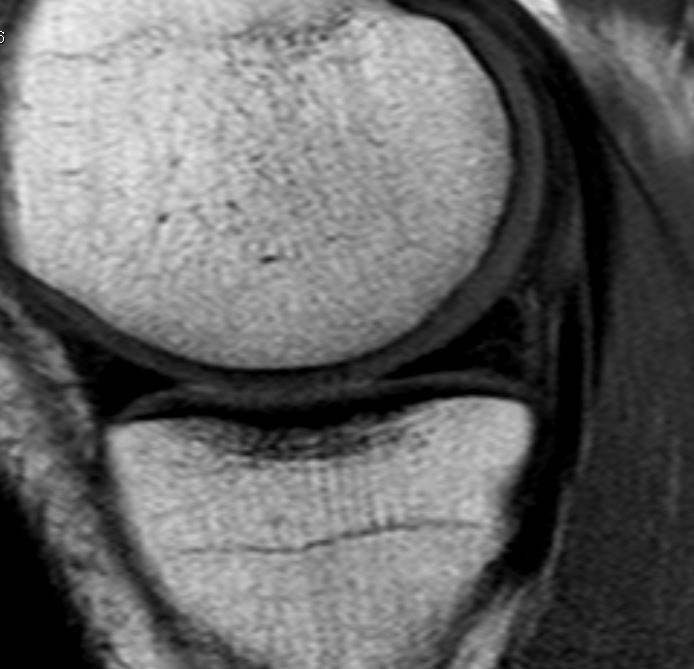

Ich lerne immer mehr Menschen mit kaputten Knorpeln kennen. Besonders vom Abbau betroffen sind die Knie und die Bandscheiben.